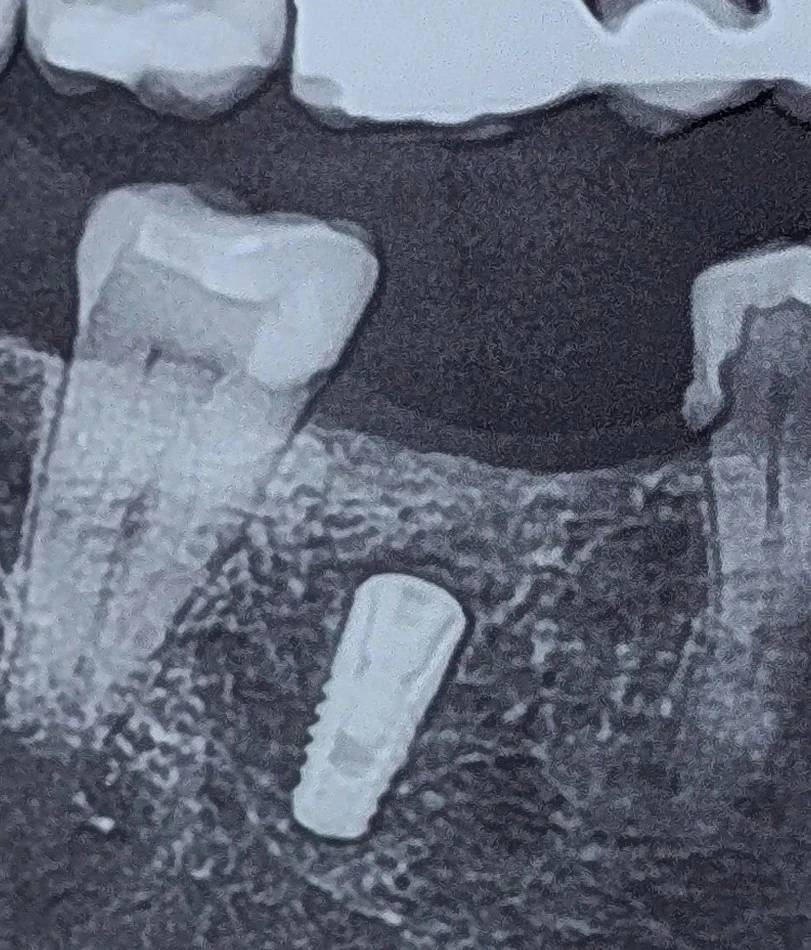

ایمپلنت در ساکت دندان کشیده شده و به صورت fresh socket قرار داده شده بود.

اینتگریشن صورت گرفته بود و در نگاه اول شرایط قابل قبول به نظر میرسید.

اما موقعیت آن—چند میلیمتر پایینتر از سطح استخوان— نکتهای بود که مسیر درمان را تغییر داد.

در این کیس، عمق بیش از حد ایمپلنت باعث شده بود پلتفرم در موقعیتی بسیار اپیکال قرار بگیرد؛

و همین موضوع در فاز پروتز چالشهای متعددی ایجاد میکند.